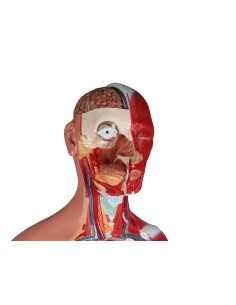

Scopri il Mondo dell’Anatomia con Modelli anatomici di Precisione

Modelli Anatomici Dettagliati per Ogni Necessità

Dal cranio in 22 parti con incastri magnetici ai modelli di colonna vertebrale, da quelli di articolazioni a quelli di cuore, ogni pezzo della nostra collezione è progettato per un’immersione totale nello studio dell’anatomia umana. I nostri modelli, realizzati tramite scansioni di ossa vere, garantiscono un’esperienza tattile autentica e una fedeltà di peso quasi identica agli originali.

Strumenti Didattici Innovativi per l’Educazione e la Pratica Medica

Essenziali per studenti e professionisti, i nostri modelli anatomici sono strumenti didattici che permettono di osservare le strutture anatomiche con precisione, eliminando la necessità di dissezioni o studi invasivi. Sono inoltre utili per spiegare ai pazienti le patologie, rendendo la comunicazione più efficace e risparmiando tempo prezioso.